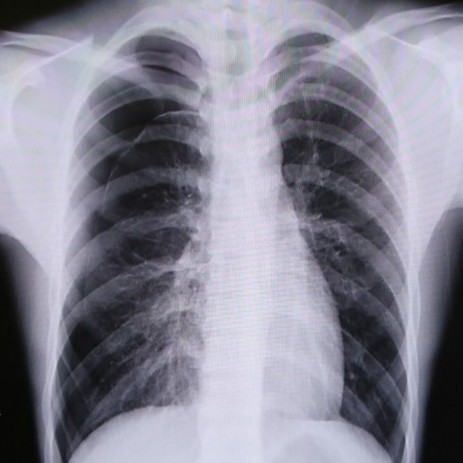

実際の写真がコチラです。

見づらいですが、片方の肺は肺紋理と呼ばれる血管や気管支などの筋が肋骨まで届いていません。

CTを撮れば一目瞭然です。

まずは、経過を見るために何日間かレントゲン写真を撮ります。

空気の層が少なくなっていけば穴が塞がっていると考えられます。